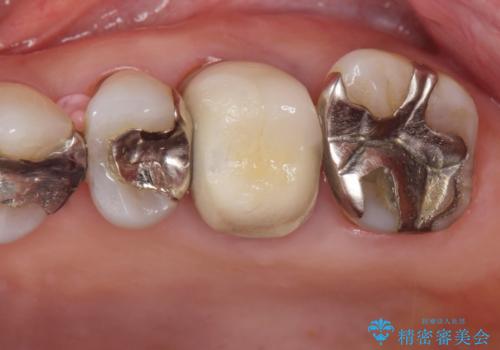

70代女性 段差のある被せ物のやり替え

- 左下の大臼歯(6番)の根の治療を行いました。

後方の歯が欠損していた為、インプラントをお勧めしましたが希望されませんでした。

その代わり、現在ある歯をしっかり治療することになり、左上下の治療を行っています。